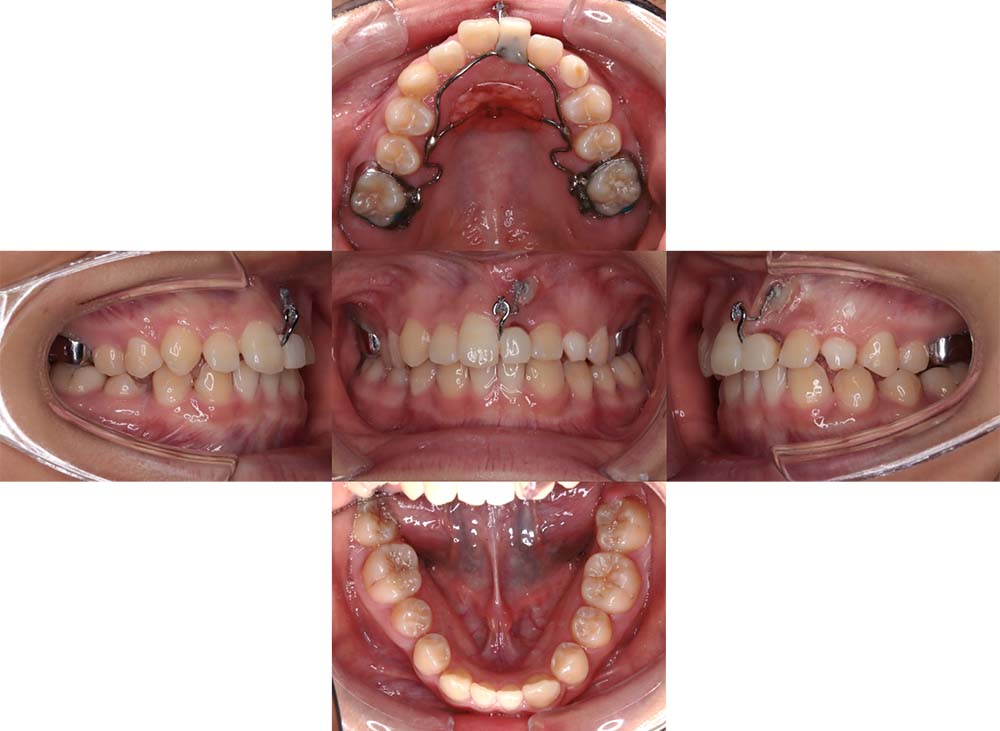

症例04

| 主訴 | 歯並びのガタガタと出っ歯が気になる。 |

| 診断名あるいは主な症状 | 上顎前突、叢生 |

| 年齢/性別 | 16歳・女性 |

| 矯正ステージ | 大人の矯正治療 |

| 治療方法 | ワイヤー矯正 |

| 抜歯部位/抜歯有無 | 抜歯 |

| 治療内容 | 抜歯したスペースを使用し、ガタガタの改善と上下顎前歯を後退させた。 |

| 費用 |

85万円程度(2025.10時点の料金となります。) ※矯正基本料金、審美ブラケットを含む |

| 治療期間 | 2年5ヶ月 |

| 主なリスク・副作用 | 痛み、歯根吸収、歯肉退縮、虫歯、後戻り |